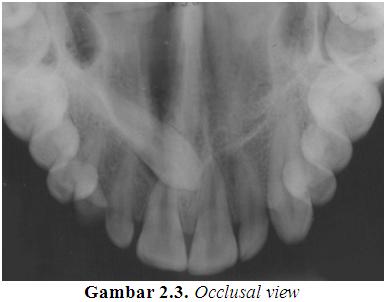

Occlusal view

Occlusal view yang ditunjukkan pada Gambar 2.3 diambil ketika ada keinginan untuk menampakkan kerangka atau anatomi patologis baik dari dasar maupun langit-langit mulut. Film occlusal berukuran sekitar tiga atau empat kali ukuran film yang digunakan untuk mengambil sebuah periapical atau bitewing view yang dimasukkan ke dalam mulut sehingga memisahkan gigi maxillary dan mandibular secara keseluruhan, dan film terpapar baik di bawah pipi maupun di siku bawah dari puncak hidung.